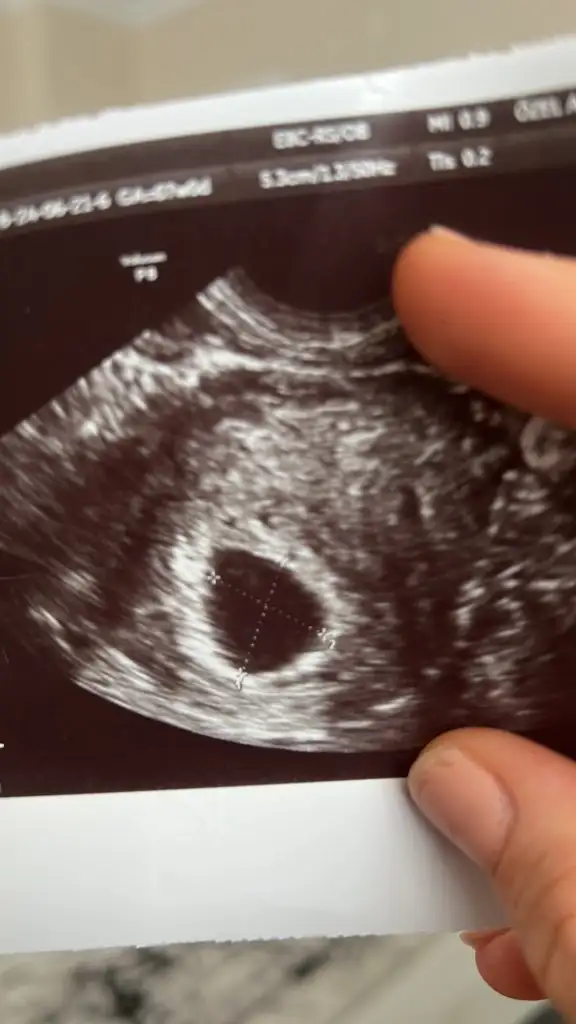

Yok kese her gittiğim de düzenli gelişiyor hatta yolk sac da sonradan çıktı doktora göre keseye göre gec döllenme imkansız dedi iyice karıştı kafam . Fotoğraftaki ilk gözüken direk kürtaj dediği kese 4 gün sonrada yukarıdaki fotoğraftaki gibi yolk sac görüldübenim son regl 4 mayıs. 5+3te kesem 1.25 cm iken ne bebek ne yolk sac vardı bende. pazartesi günü 7+6 da yani 10 gün sonra bebek ve kalp atışı görüldü. gec döllenme olabilir yani kese boyu hala kücük bence. he kese gelişmiyorsa o zaman bilemem.

kaç cm burada göremiyorum ama kese boyundan zatem kaç haftalık olduğu anlaşılıyor. yani kese boyu normal haftanızla uyumluysa doktorun böyle düsünmesi normal. yani 7.haftada bebek görünmeli aslında. ben dediğim gibi 6+6da gördüm ve gayet de net bir sekilde fasülye kadar bir seydi. bilemiyorum ya inşallah güzel olur. doktor daha iyi bilir tabii ki ama bence baska bir doktoru da deneyinYok kese her gittiğim de düzenli gelişiyor hatta yolk sac da sonradan çıktı doktora göre keseye göre gec döllenme imkansız dedi iyice karıştı kafam . Fotoğraftaki ilk gözüken direk kürtaj dediği kese 4 gün sonrada yukarıdaki fotoğraftaki gibi yolk sac görüldü